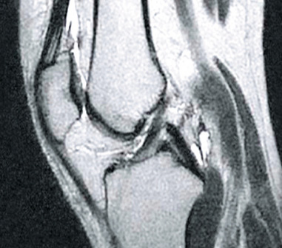

PRZED

PO

Na zdjęciu po lewej widać puste przestrzenie w obrębie torebki stawowej powstałe na skutek zbytniego uwodnienia tkanki. Po kuracji struktura mazi stawowej się odbudowała (zdjęcie po prawej), odzyskała lepko-sprężystą konsystencję i właściwości poślizgowe. Kości są odpowiednio „naoliwione”, dzięki czemu nie trą o siebie, ponieważ funkcje amortyzujące stawu zostały przywrócone.